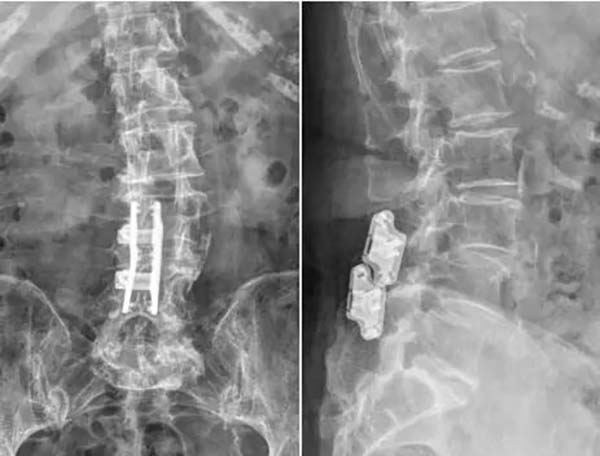

▲棘突间固定装置

手术当日,脊柱外科(骨四科)团队为患者施行手术。术中团队操作精细,全程密切配合,仅1小时30分钟手术顺利结束。术后患者恢复良好,腰腿痛明显好转。术后三天患者即可下地行走,术前存在的下肢疼痛、麻木及双腿沉重感均得到明显改善。